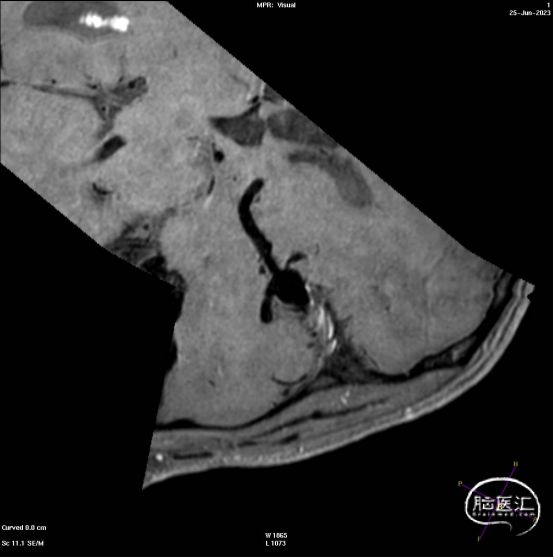

此为左侧大脑中动脉瘤,近端血管极为迂曲,瘤体有突出的子囊,动脉瘤与载瘤动脉有一定夹角,动脉瘤呈上窄下宽形状,M2段下干从瘤颈近端发出。

动脉瘤平均宽度5.41mm, 最小高度为3.71mm,瘤颈约为4.94mm,使用WEB™ SL 6*3mm瘤内扰流装置进行栓塞治疗。

释放WEB™:缓慢推出WEB™从种子至萌芽状态,继续向瘤腔内远端缓慢推送WEB™至萌芽至开花间状态;将WEB™和VIA™送至瘤顶,固定WEB™推送杆回撤VIA™,WEB™完全释放。

经造影可见WEB™尺寸合适,贴合瘤壁,覆盖瘤颈,且下支M2段分支及其他分支血管血流通畅。

解脱后,再次造影和Dyna-CT评估,可见动脉瘤瘤腔内有明显造影剂滞留,分支血管血流正常。

大脑中动脉瘤充分栓塞,瘤颈残留,WEB™充分栓塞。WEB™被压缩且位置偏转,分支血管有影响。